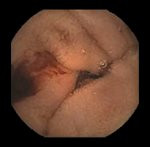

Die Kapselendoskopie bietet die Möglichkeit, den mehrere Meter langen Dünndarm auf sehr schonende Weise zu untersuchen. Nötig ist dies u.a. bei unklarer Eisenmangelanämie oder Blutungen aus dem Verdauungstrakt, wenn einen Magen- und Darmspiegelung zuvor keine Blutungsquelle finden konnten. Auch bei Morbus Crohn oder einer Zoeliakie kann die Untersuchung unter Umständen sinnvoll sein. Der Patient schluckt eine Minikamera in Form einer Kapsel, die in etwa so klein wie eine größere Tablette ist. Die Bilder werden an ein Aufnahmegerät übertragen und aufgezeichnet, die Kapsel nach der Darmpassage ausgeschieden. Die Auswertung der Bilder erfolgt dann durch den Arzt im Nachhinein. Mit der Pillcam SB3 der Firma Given Imaging steht das derzeit modernste System zur Verfügung.

Alle Bilder mit freundlicher Genehmigung der Fa. Covidien